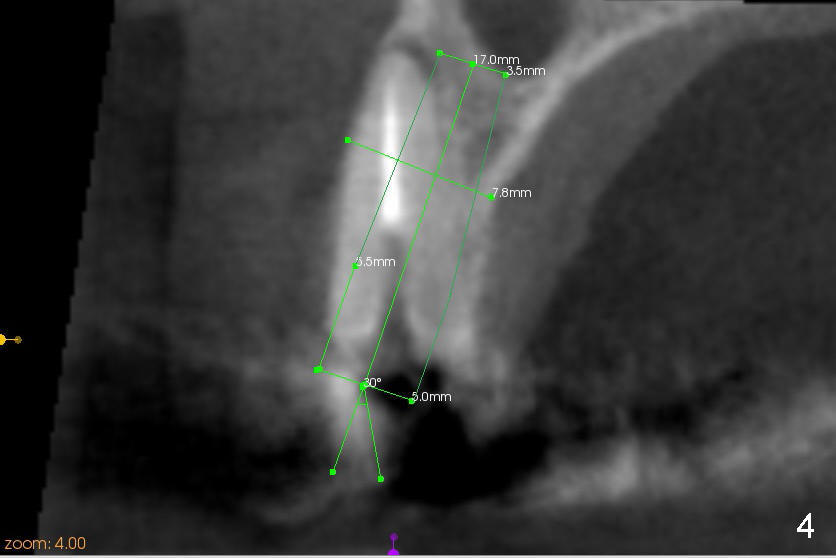

CBCT studies reveal that the implant perforates the buccal plate at the site of #7 and that there is still enough bone to support 3.0x17 mm one piece implant (Fig.2,3).  There is limited bone apical to the tooth #6.  The implant should be at least 17 mm for bone level and 14 mm for tissue level (Fig.4) or preferably 20 mm with sinus lift (Fig.5).  The diameter will be 4.5 mm (Fig.6) or 5 mm (Fig.4.5).